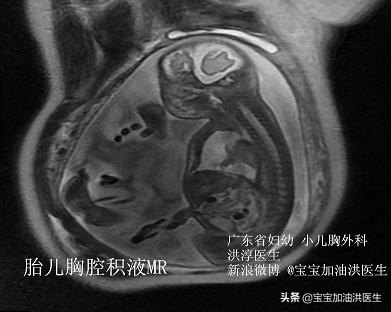

谈谈胎儿-新生儿胸腔积液的可能原因。

在胎儿时期,我们就可以通过各种手段,去判断小朋友的情况